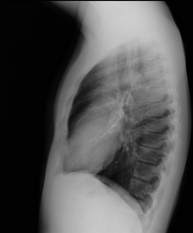

Tècnica que usa els raigs X a través de la qual s'obtenen imatges de la columna cervical per al seu estudi. Indicacions: traumatisme, dolor cervical. - RX Columna dorsal

Tècnica que usa els raigs X a través de la qual s'obtenen imatges de la columna dorsal per al seu estudi. Indicacions: traumatisme, mal d'esquena. - RX Columna lumbar